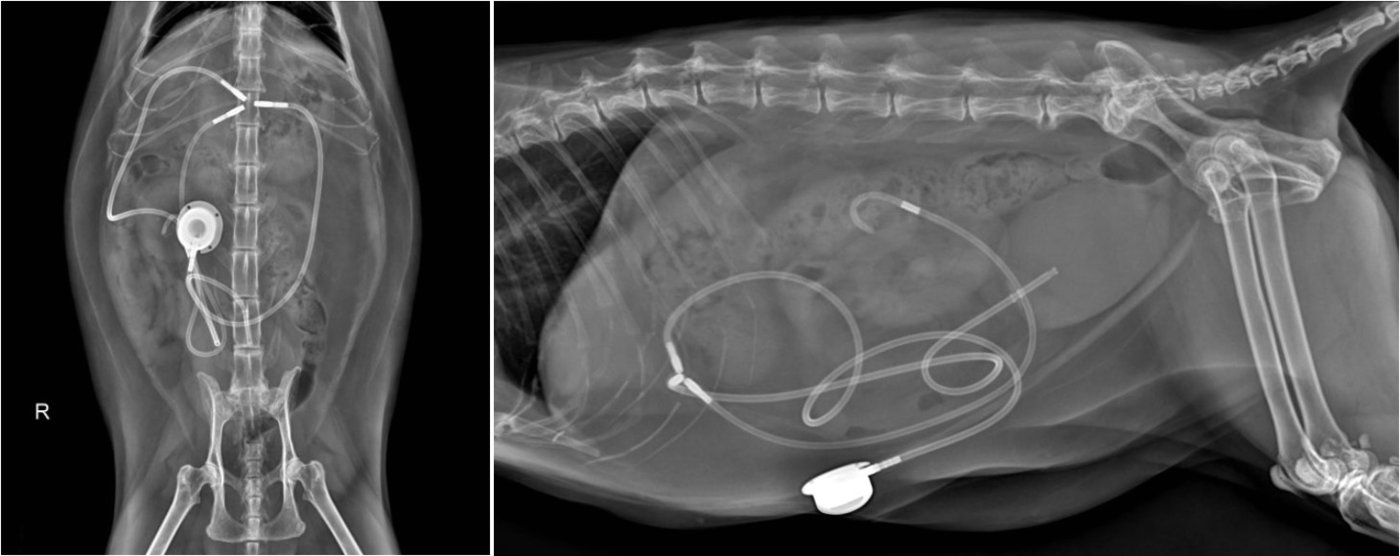

본문 이미지 - 인공 요관 우회술을 한 고양이의 방사선 사진 (동물병원 제공) ⓒ 뉴스1

인공 요관 우회술을 한 고양이의 방사선 사진 (동물병원 제공) ⓒ 뉴스1